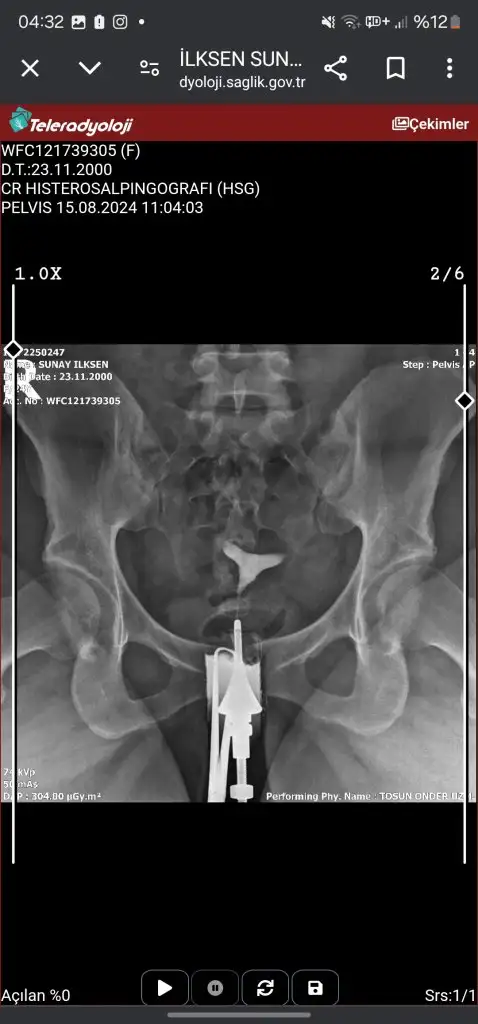

Canım tek tüpün kapalı galibaKızlar acil sonucuma bakarmısınızz ben hiçbirşey anlamıormm